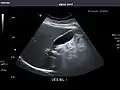

Kidneys: Right and left kidneys measure 11.5 cm and 12 cm in length respectively. No hydronephrosis. Small left lower pole kidney cyst.

Right kidney

Left kidney